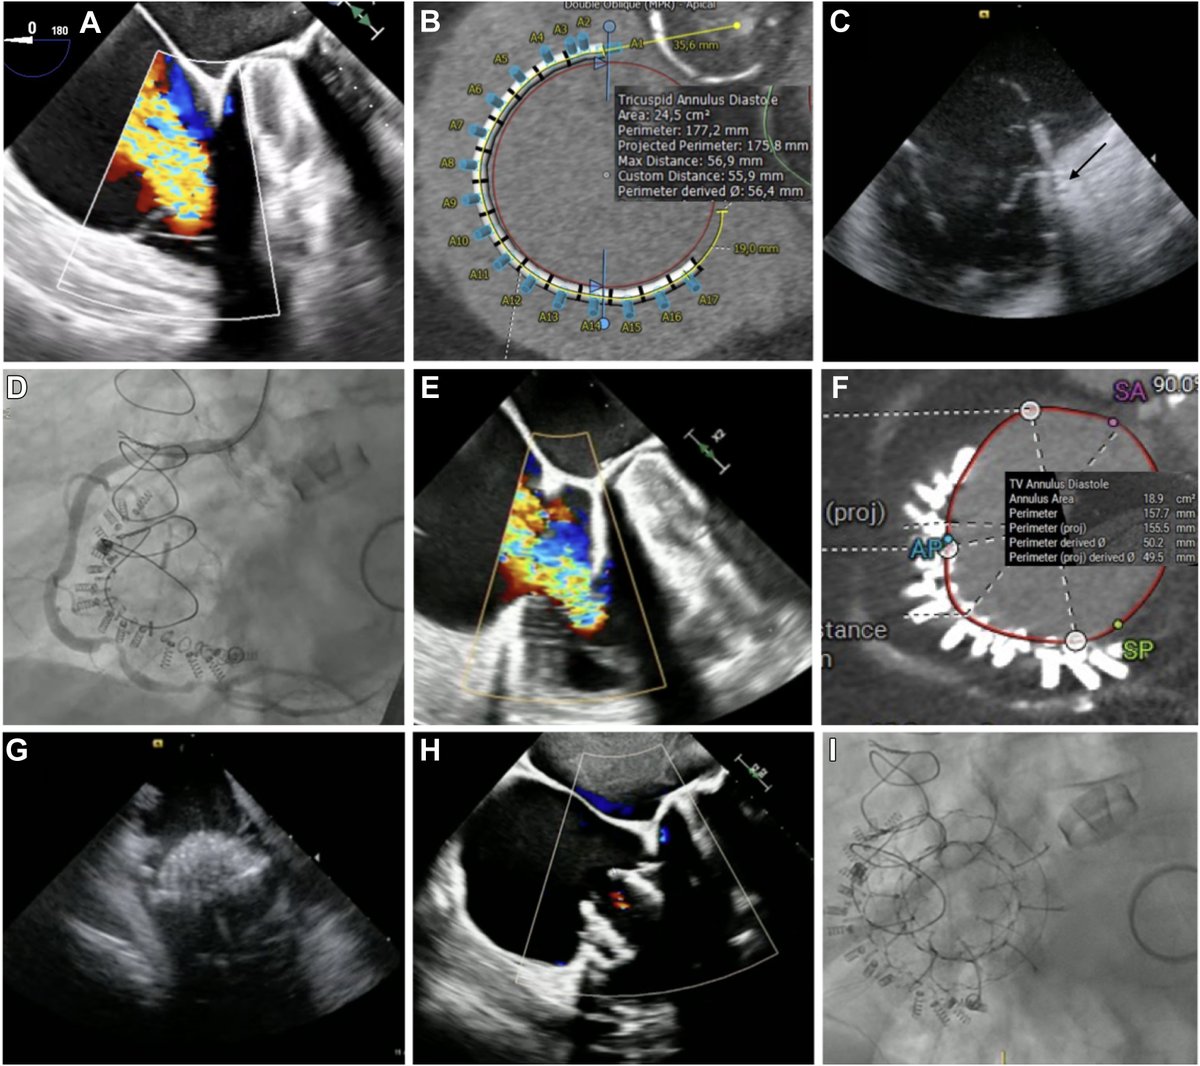

Outstanding 11/10 issue of #JACCINT @JACCJournals on #Tricuspid and #Mitral transcatheter interventions including M-TEER, T-TEER, #TMVR, #TTVRR, including #AltaValve 6m EFS outcomes, conduction disturbance mechanism post #TTVR, 3D annular changes post T-TEER, L and R heart